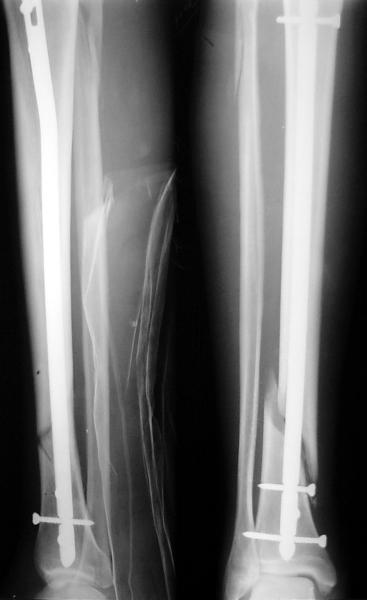

JOM> Кстати, если можно пошлите послеоперационный снимок.

Ok. А также и следующий, в 3 месяца.

Это наглядная демонстрация возможности ранней полной нагрузки при нестабильном по оси повреждении, причем не в самых благоприятных механических условиях - при плохом сопоставлении, со слабым фиксатором.

Сверху - один статический винт, а снизу - три. Что раньше сломается? Конечно, он потом и нижние сломал, и Вы правы, если бы верхний динамичесий винт уже уперся бы в нижний край отверстия, будь гвоздь подлинее, перфорировал бы сустав как пить дать.

Как я уже говорил, мы сделали выводы из этого и других подобных случаев. Очевидно, решений проблемы два - либо уменьшить нагрузку, либо увеличить прочность фиксатора. Первое решение работает не со всеми больными, так что пошли по второму пути - мы больше не используем гвозди с запирающими винтами диаметром 4 мм.